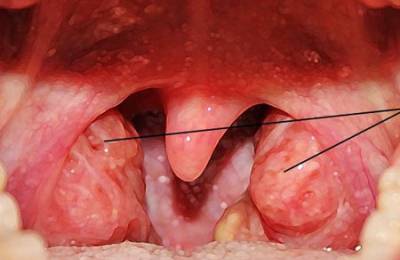

- миндалины покрываются налетами или пузырьками и отекают;

- миндалины отекают и краснеют, налетов нет;

Грибковая ангина без температуры встречается очень часто. Ее вызывают дрожжеподобные грибы и проявляется она неприятным запахом изо рта и белыми налетами на миндалинах, которые могут распространяться на язычок и заднюю стенку глотки.

- миндалины красные, отечные покрыты налетами, язвами или пузырьками в зависимости от вида ангины.